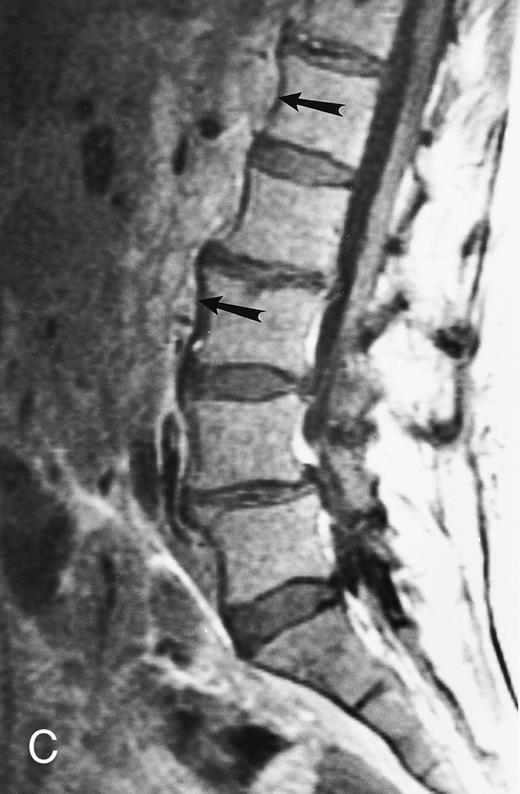

A 75-year-old woman with Waldenstrom macroglobulinemia: T1-weighted (600/20, TR/TE) axial (A) and sagittal T1-weighted (600/20, TR/TE) precontrast (B) and postcontrast (C) MR images of the lumbosacral spine. Note diffuse pattern of marrow infiltration and enlarged retroperitoneal lymph nodes (arrows). The abnormal marrow is isointense to the intervertebral discs on the precontrast image and enhances markedly becoming hyperintense to the discs on the postcontrast image.

A statistically significant relationship was shown between grades of contrast uptake by the abnormal marrow on enhanced MR images and values of hemoglobin and lymphoplasmacytoid infiltration indices of the bone marrow.38 Increasing grades of contrast uptake on enhanced MR images correlated with increasing tumor burden. A direct correlation was found between decreased enhancement of the marrow on posttreatment MR images and degree of clinical response.38 The application of quantitative analysis of the involvement of the marrow on MR images to the assessment of response to therapy in patients with macroglobulinemia may be of value in individual problem cases.